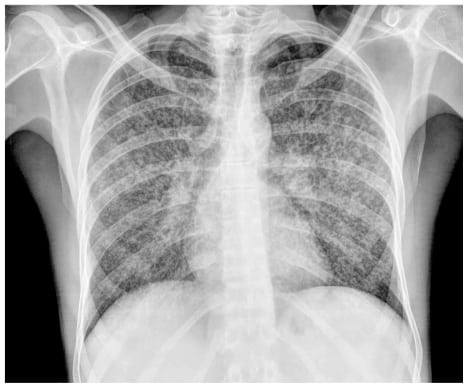

Gambaran bercak putih pada seluruh paru dalam pemeriksaan rontgen dada.

Selain itu, pemeriksaan lainnya dapat berupa rontgen dada. Sesuai dengan namanya, tuberkulosis miliaria berwujud seperti bintik-bintik pada paru. Dokter juga dapat melakukan pemeriksaan computed tomography scan (CT scan) untuk melihat gambaran penyakit pada paru dengan lebih detil.